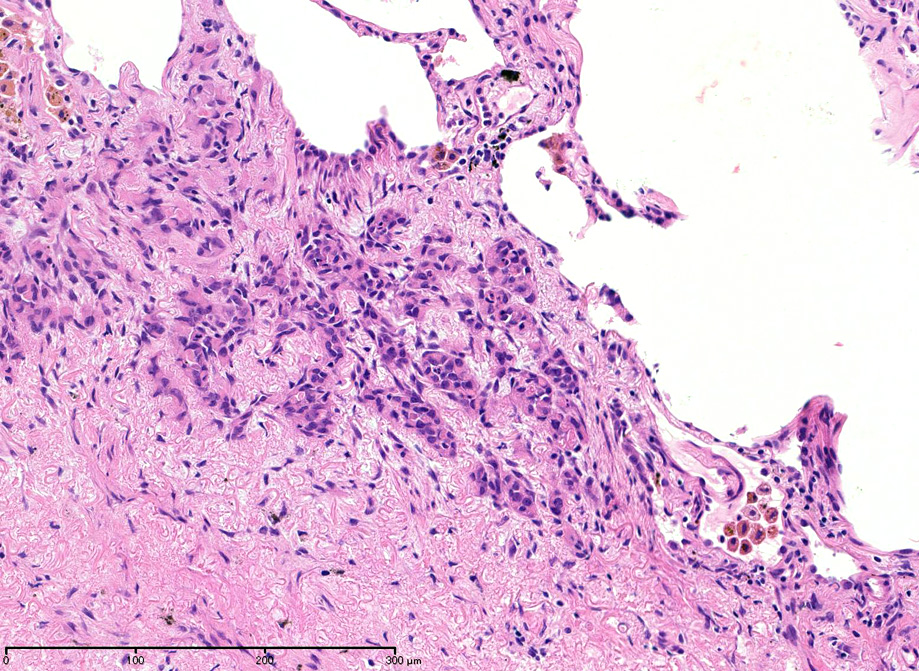

hyperchromaticな類円ないし多角の核で好酸性の広めの細胞質をもつ上皮様細胞が増殖している。右図では血管内を占拠するように腫瘍細胞が認められる。

左図:腺腔様の裂隙が胞巣内にみられ, 凍結標本だと腺癌との区別がむずかしい。